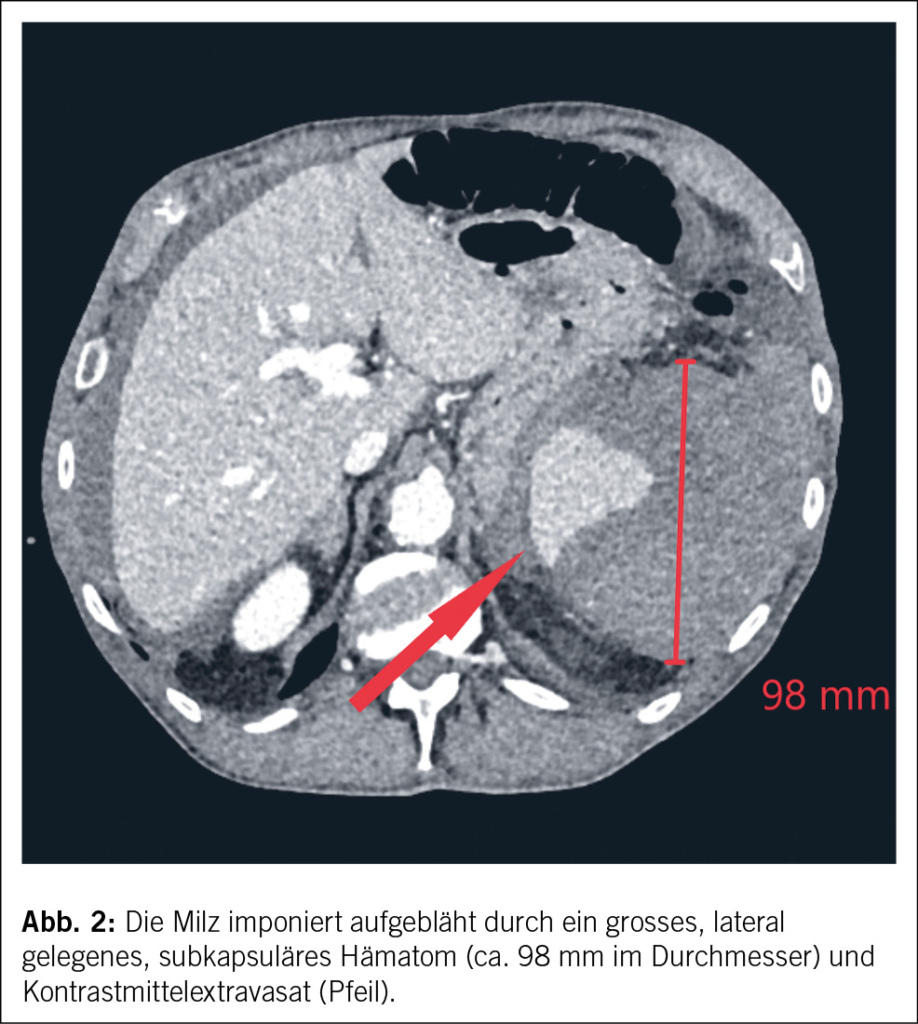

- Eine seltene Ursache der Milzruptur